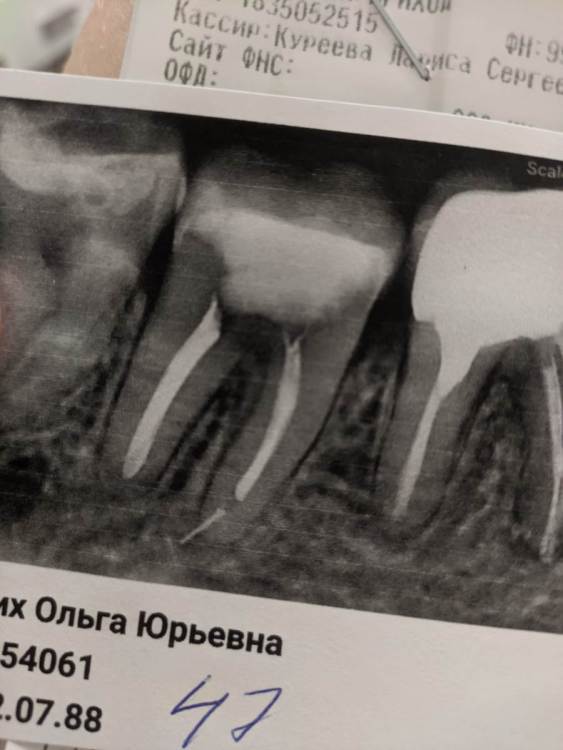

Meolia Опубликовано 8 октября, 2021 Поделиться Опубликовано 8 октября, 2021 4 месяца назад депульпировали 47 зуб. Особых показаний не было, просто постоянная поверхностная чувствительность зуба больше года - со всех сторон, не острая, но достаточно ощутимая. Во время обработки каналов обломок файла остался в корне зуба. После депульпирования зуб продолжает болеть, характер боли такой же, как и до депульпирования - реакция на надавливание/жевание. Последний приём был 3 месяца назад, решили ещё раз обработать каналы, заложить лечебную пасту на 2-3 месяца, закрыть тонкой световой пломбой и подождать. За это время чувствительность только усилилась. Консультировалась у эндодонтистов в разных клиниках, везде говорят, что зуб хороший, трещин нет, поводов для беспокойства нет, нужно просто ещё раз пролечить и поставить нормальную световую пломбу. Первый вопрос: какие перспективы у этого зуба? То, что файл не достать, я поняла. Есть смысл ещё лечить или сразу удалять? Второй вопрос. В одной стоматологии предположили, что в случае благополучного лечения через какое-то время (год-два) все равно нужно будет ставить коронку. Есть ли смысл ставить коронку на перфорированный депульпированный зуб? Или опять же логичнее его удалять? Ссылка на комментарий

Meolia Опубликовано 20 ноября, 2021 Автор Поделиться Опубликовано 20 ноября, 2021 @Карен Аванесов Большое спасибо за ответ. Месяц назад поставили нормальную пломбу. Во время чистки каналов сильнейшая боль где-то в верхушке(как и в предыдущий раз). Врач предполагает, что все-таки это похоже на трещину. Предложил снова выжидать, возможно пройдёт, либо нужно просто привыкнуть к чувствительности зуба. Но дело в том, что чувствительность хоть и не острая, но достаточно сильная, возникает даже если просто провести пальцем по зубу, при этом как будто болит полностью весь зуб с корнями, не только поверхность. Не знаю связано или нет, но в последнее время стали появляться тупые тянущие боли (не часто, не острые) в глубине десны где-то под этим зубом. Можно ли что-то предположить по такому описанию? Заранее спасибо. Ссылка на комментарий